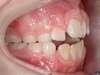

Cas 4 : Description

Chevauchement sévère. Traitement multibague sans extraction.

Avant

Après